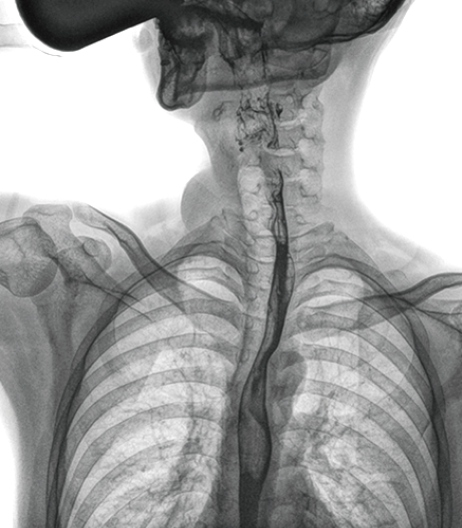

視頻保存與回放

動(dòng)態(tài)DR具有視頻保存、回放功能,可以完整的記錄整個(gè)透視動(dòng)態(tài)圖像,便于重復(fù)觀察、分析,減少遺漏。該功能在食道造影中優(yōu)勢(shì)明顯:患者口服造影劑后流速很快,傳統(tǒng) DR 的盲拍或是數(shù)字胃腸造影很難抓拍到,需要患者反復(fù)喝造影劑,而動(dòng)態(tài) DR 視頻實(shí)時(shí)保存回放,既減少漏診誤診又減輕患者痛苦,也更加節(jié)省醫(yī)生時(shí)間。

上消化道造影高清圖像